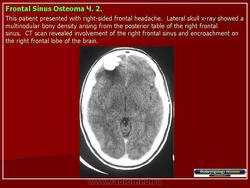

Компактные остеомы обычно располагаются в костях лицевого скелета. Остеомы могут быть обнаружены в любом возрасте, однако время обращения к врачу не соответствует началу заболевания. Вследствие медленного роста и отсутствия клинических проявлений остеомы нередко диагностируют только у взрослых, которые помнят, что заболевание возникло у них еще в детстве.

Рентгенодиагностика остеом, как правило, не представляет трудностей. Рисунок опухоли является продолжением рисунка самой кости. Деструктивные изменения и нарушение коркового слоя всегда отсутствуют.

Остеома лобной пазухи.